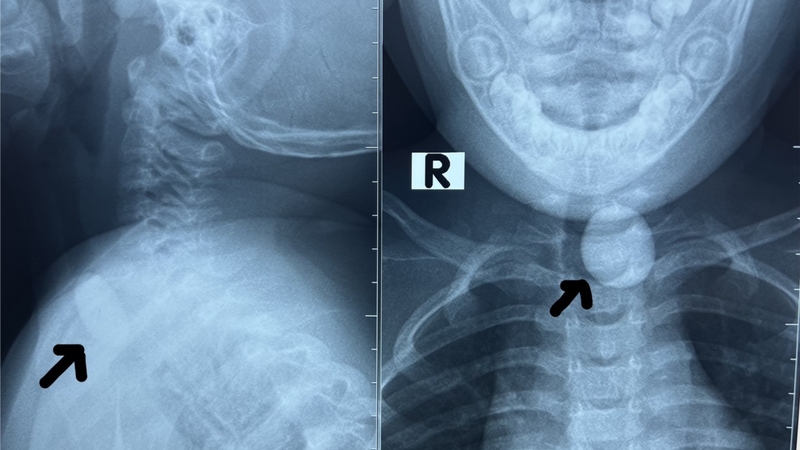

Cách xử lý khi bị dị vật thực quản

Dị vật thực quản là một vấn đề phổ biến trong quá trình ăn uống, có nguy cơ đe dọa tính mạng và tỷ lệ tử vong cao. Thường gặp nhất là xương động vật như cá, gia cầm, và lợn. Khi gặp trường hợp này, việc đi khám hoặc tìm kiếm sự tư vấn từ bác sĩ chuyên khoa Tai Mũi Họng là cần thiết để nhận được hướng dẫn về cách xử trí đúng.

Dị vật thường mắc ở thực quản tại những khu vực có ống hẹp do yếu tố sinh lí hoặc bệnh lí. Đó có thể là do cơ thắt như cơ thắt thực quản dưới, cơ thắt thực quản trên, hoặc sự hiện diện của các cấu trúc mạch máu bên ngoài như động mạch chủ dưới, động mạch dưới đòn mạng lưới, nhẫn, các khối u lành tính, ung thư, co thắt tâm vị, co thắt thực quản lan tỏa, phẫu thuật trước đó, hoặc viêm thực quản tăng bạch cầu ái toan.